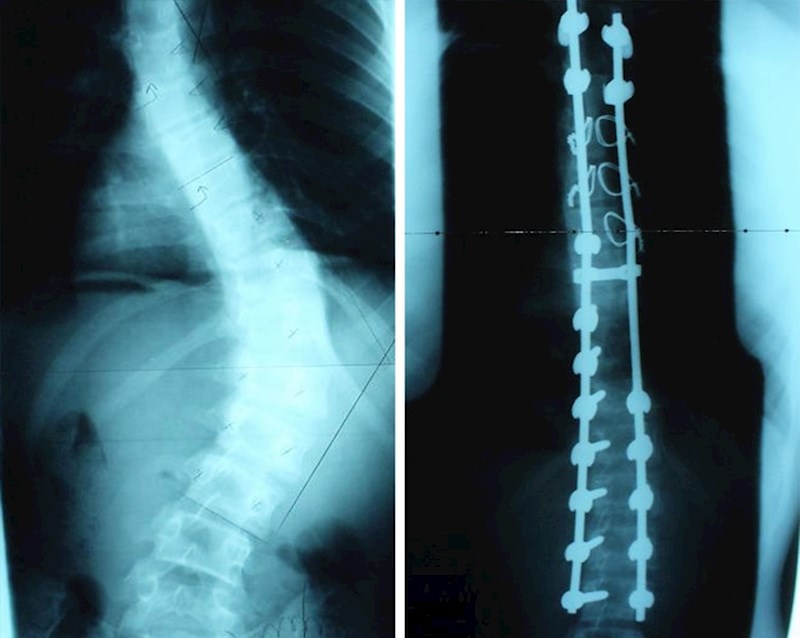

Prije i poslije operacije skolioze.